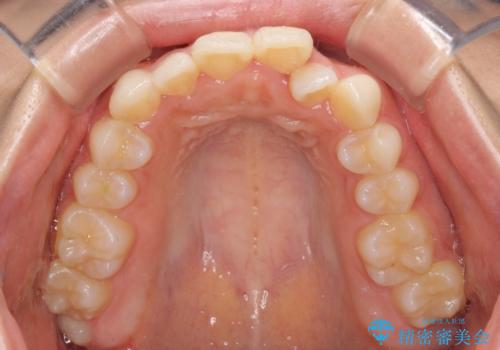

【モニター】前歯のクロスバイトをインビザラインで治療

- 前歯のデコボコとクロスバイトを気にして来院された患者様です。

上顎側切歯(上の真ん中から2番目の歯)が舌側転位している場合、インビザラインでは仕上げきれないことが多く、更には無理して動かそうとすると歯髄壊死を起こすリスクが高いと言われています。

今回は、ワイヤー装置を併用することなく、インビザライン単体で矯正治療を行うこととしました。

インビザライン特有の、奥歯の咬み合わせの問題もなく、しっかりと歯列を改善することができました。

舌側転位している上顎側切歯(内側に引っ込んでいる真ん中から2番目の歯)は、インビザラインが最も移動を苦手とする歯であり、これ以上の改善を望まれる場合にはワイヤー矯正、あるいはワイヤー矯正の併用をお勧めいたします。